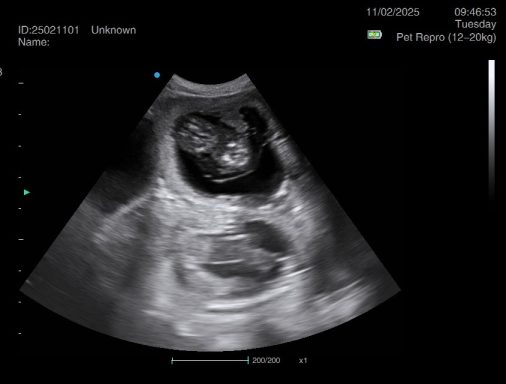

Ultrasound pregnancy scanning is a safe, non-invasive way to confirm pregnancy in dogs and cats, offering breeders and pet owners peace of mind and vital information to support responsible care. It allows us to detect gestational sacs, assess foetal development, and estimate litter size—all while ensuring the wellbeing of the animal.

Pregnancy can sometimes be detected as early as Day 18 post-mating, but scanning at this stage is not routinely recommended. Embryos are still developing and may not be clearly visible, and there is a natural risk of embryo resorption, which can lead to misleading or inconclusive results.

For the most accurate and reliable scan, we advise booking between Day 25 and Day 32, when pregnancy is more easily confirmed and foetal structures are clearer. If an early scan is performed and no pregnancy is detected, we offer a FREE complimentary re-scan after 7 days at the clinic to ensure clarity and support informed decision-making.

Our approach balances early insight with ethical care—always prioritizing the comfort of the animal and the accuracy of the results.

Gallery